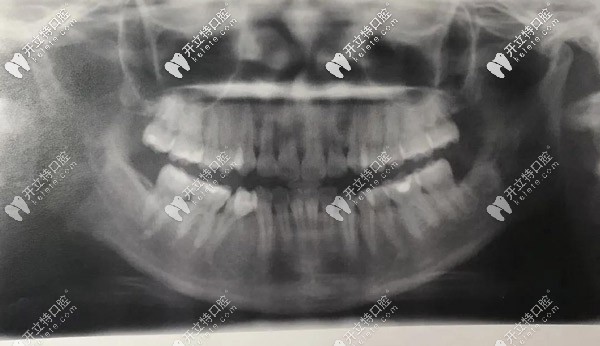

側(cè)面X光,門牙唇傾很厲害的

▲側(cè)面X光,門牙唇傾很厲害的